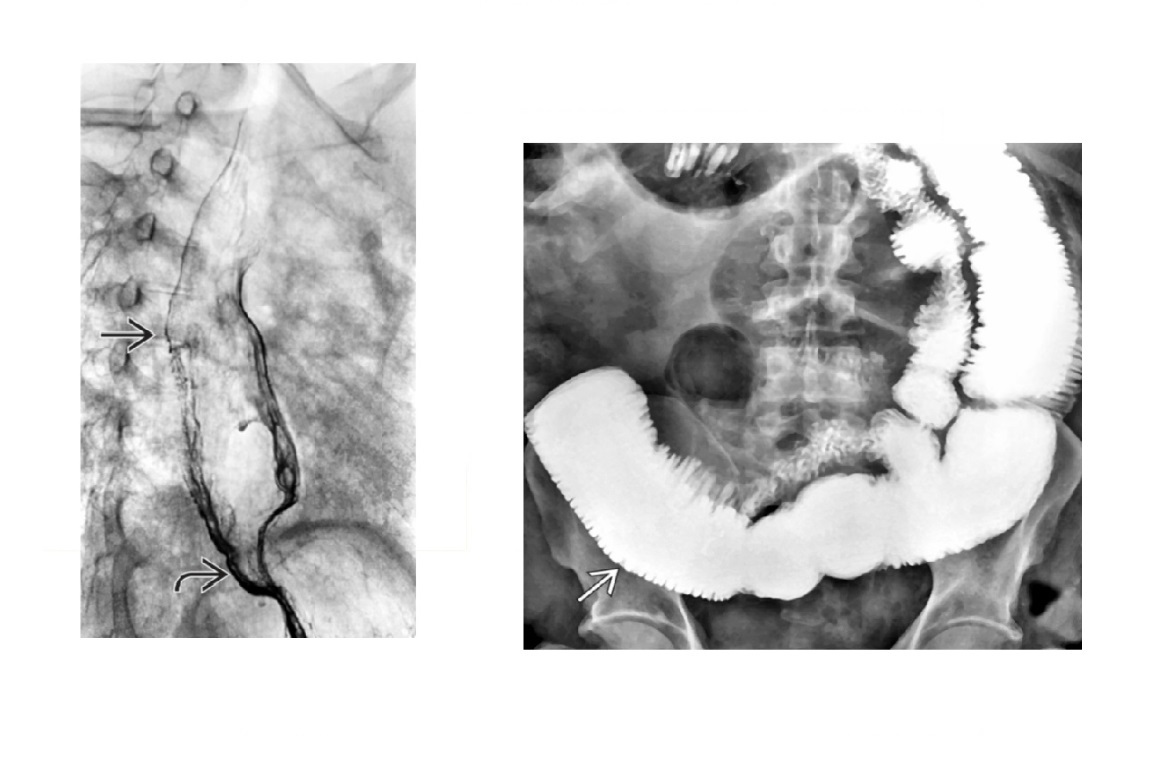

Sigmoid Vovulus Inverted U shape Ahaustra Coffee bean - cleft is double thickenss of opposed bowel loops Directed toward right upper quadrant (RUQ) or left upper quadrant (LUQ); Look for - Gas in proximal small bowel and colon Abscence of air in rectum Tend to be older patients Mx with rectal decompression

60

Caecal voluvulus Dilated, air-filled left upper quadrant or abdominal midline Haustra Single, long air-fluid level within cecum (upright or decubitus film) Moderately distended small bowel, little gas in distal colon Markedly dilated cecum that appears upside down and backward with ileocecal valve directed laterally

61